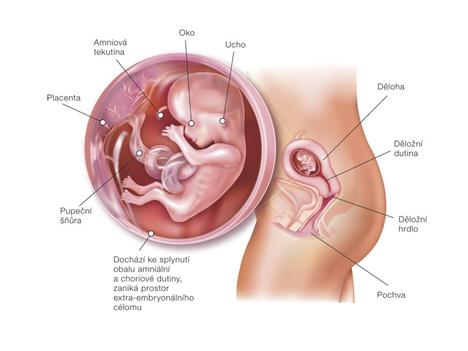

Bohužel se našel mezi mnou a přítelem určitý problém a bez odborné pomoci by jsme se vůbec nedočkali! Snad už se konečně zadařilo a našemu bobískovi, kterého mám v sobě, se bude u nás líbit a vydrží až do samého konce porodu 18.1.2011.

Při druhém pokusu jsme se s doktorkou dohodly, že nastoupím na dlouhý protokol, aby se mi vytvořilo víc kvalitních vajíček. Začala jsem stimulovat od půlky února a koncem dubna šla na odběr folikulů. A taky že to pomohlo, vytvořilo se víc kvalitních vajíček. V Sanatoriu jsem řekla embryologovi, jaký jsem měla posledně problém, a sama mi nabídla, že teda necháme PK na 5 dnů, aby viděli, jak se vyvýjejí a jak to zvládají. 1.5.2010 jsme si jeli do Prahy pro naše embroušky, dokonce vydrželi ještě další dva, které mi dali zamrazit do zálohy.